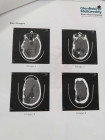

Just a few weeks ago, our lives were turned upside down. Inayatullah had to undergo emergency brain surgery after a sudden and critical health episode. Thankfully, the doctors were able to save his life, and for that, we are forever grateful.

Inayatullah is now admitted at Glenfield Malla Reddy Brain and Heart Hospital in Hyderabad, where he is undergoing intensive rehabilitation therapy. He’s bravely trying to relearn how to move, speak, and carry out even the most basic activities. Each day is a challenge—but also a step forward. His spirit is strong, but his body needs time, care, and consistent medical support to recover.